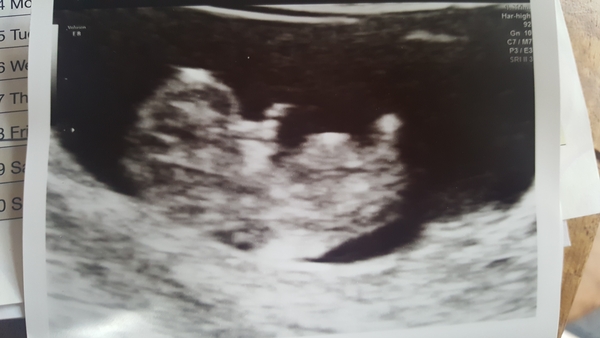

12 week scan done and all ok! Phew, such a week. Measurements had me at 12+5, which is bang on what I thought.

Lovely scan @Ohnonotanotherusername! Proper wee baby! ☺️ Xx

@BeeKeeping thanks! It's so weird! We could see it's little fingers on the screen. Absolutely nuts.

Loving the scan pics! Still haven’t even got mine scheduled in!

@Ohnonotanotherusername lovely picture, very pleased for you! Do you mind me asking if you drank the obligatory pint of water before? I'm worried about my bladder holding for mine tomorrow!

Those scan pics look amazing!

@Annie264 I did and my bladder was too full, so I had to empty it quite a bit. The sonographer said to me that your bladder only needs to be about half full. Good luck tomorrow!